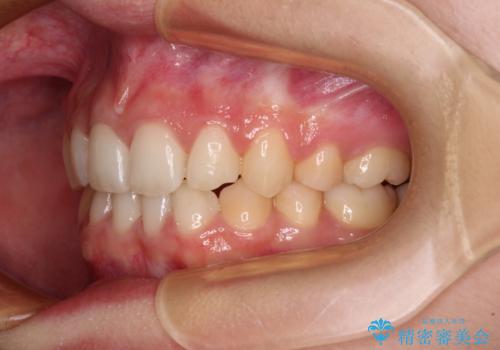

- 下顎前歯が欠損しており、前歯がデコボコとなっている歯並びを気にして来院された患者様です。

下顎の左右側切歯2本が欠損しており、上顎歯列がデコボコとなっている状態でした。

下顎歯列に対して上顎歯列が相対的に大きくなっているため、デコボコとなっているだけでなく、下顎前歯が見えなくなるくらいのディープバイトにもなっていました。

通常の抜歯矯正と抜くべき歯の位置が異なるため、咬みにくさが残ってしまうのではないかと懸念されましたが、咬み合わせに違和感なく、スムーズに治療を終えることができました。